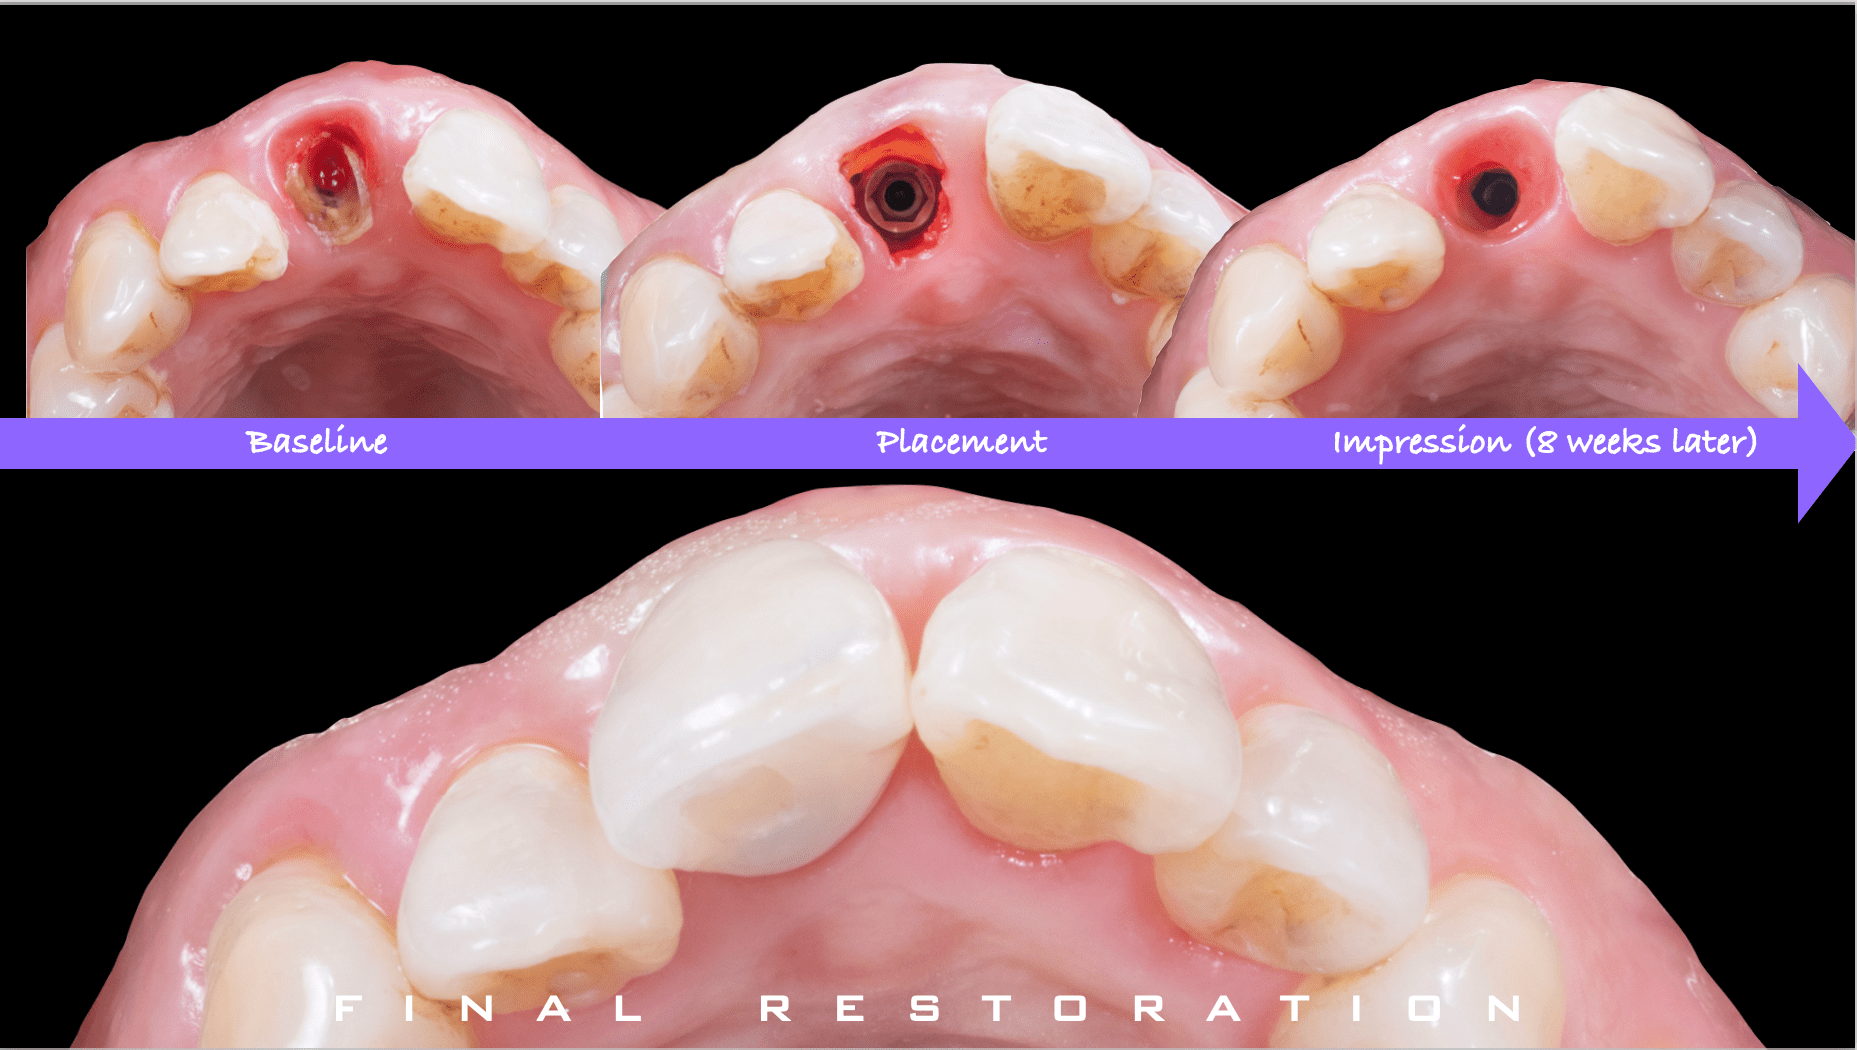

症例紹介29:インプラント治療/前歯_ソケットシール《50代女性》

治療内容:食事中に前歯が破折し、治療を希望し来院。

上顎:折れた歯を見ると、一部被せ物に歯が残っており保存不可能な状態。

上顎:歯には太い土台が入っており、折れて保存不可能な状態

最終補綴

上顎:フルジルコニアスクリューリテイン

リスク:残っている歯の一部を残してインプラントを入れることによって、歯茎が下がるのを抑えることができます。